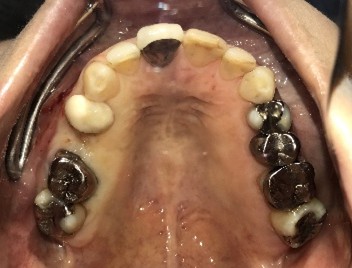

治療内容

インプラントを2本埋入しました。

所感

以前、1本歯がないところを、欠損の両側に被せ物をしてつないだブリッジでした。その2本のうちの前方の歯が歯根の破折を起こし、抜歯になり2本の欠損になりました。この2本の欠損を補う方法には、部分入れ歯、再度ブリッジ、インプラントの3つの方法があります。部分入れ歯もブリッジも欠損部分の負担をほかの歯に負わせるため、支台になった歯は負担が大きくなり、虫歯、歯周病、歯根破折の危険性が高まり、さらに歯を失うことになります。インプラントは、それ自身が単体で植立しているため他の歯に負担を負わすことがありませんので、咬合を回復させるだけではなく、他の歯を守る役割もあります。今回もX-Guideを使った埋入で、安心安全に行うことできました。

インプラント2本:¥363,000×2本=¥726,000(税込)

Before

After